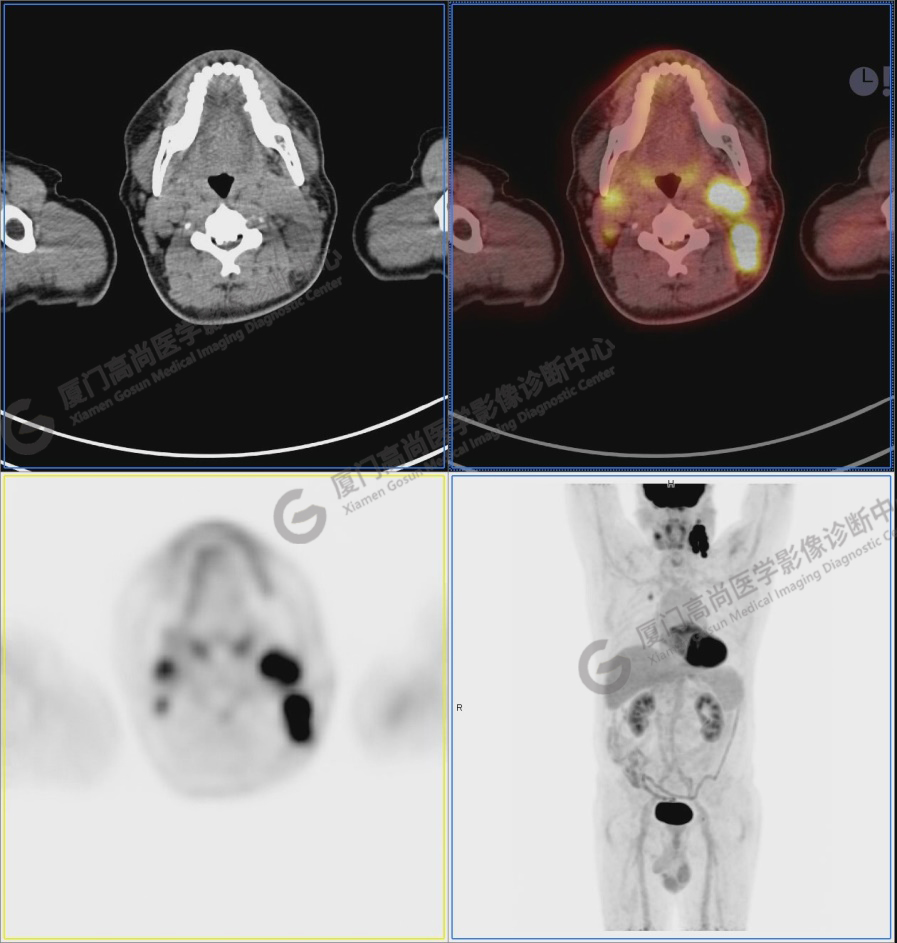

圖1:PET/CT全身圖像

圖2:雙側(cè)頸部多發(fā)增大淋巴結(jié),代謝不同程度增高,考慮為轉(zhuǎn)移。